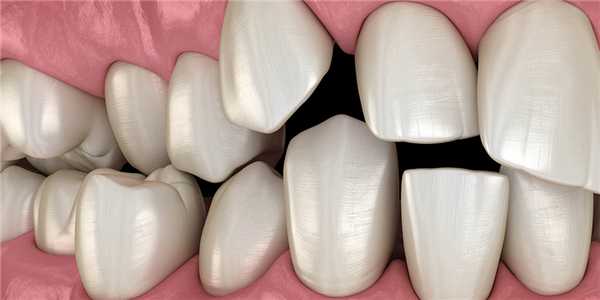

Если имеются нарушения роста челюстей или нарушения в прорезывании зубов, то это может привести к формированию неправильного прикуса. Например, к скученности зубов, это происходит, если постоянные зубы прорезывались вовремя и крупные, а рост челюсти приостановился. Иногда нарушение роста челюсти может закончиться отсутствием клыков, резцов или премоляров или же формированием промежутков и диастем.

Симптомы неправильного прикуса у детей

К очевидным признакам неправильного прикуса у ребенка следует отнести выдвижение челюстей вперед или назад, неровные зубные ряды, чрезмерная скученность зубов, гипердентия (наличием «лишних», сверхкомплектных зубов), дистопия (неправильное расположение зубов), наличие диастем и трем между зубами. Дети с неправильным прикусом могут жаловаться на трудности с жеванием и глотанием пищи, постоянное прикусывание языка или щек, боль в челюсти и мышцах лица, регулярные головные боли.